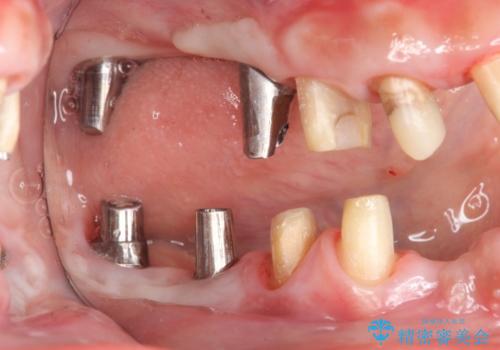

- これまで悪くなっては歯医者に通い、その都度治療を受けてきたがどんどん悪くなる痛くてしっかりと噛めない、これを機にしっかりと噛めるような治療を受けたいと希望され来院されました。

保存不可能な歯の抜歯→インプラント治療、根管治療、精密なセラミッククラウンの製作を行い長期的に安定し、審美的で機能的な治療を計画します。

歯が悪くなるたびにその都度治療を行うと、付け焼き刃の治療となりやすくまた横の歯が悪くなってしまった場合に再治療が必要となったり延々と治療が続くことがしばしばです。

隣接する歯や、残すことのできない歯をインプラントにしっかりと置き替えていくことで安心して長期にしっかりと噛める口腔内環境を達成することができます。